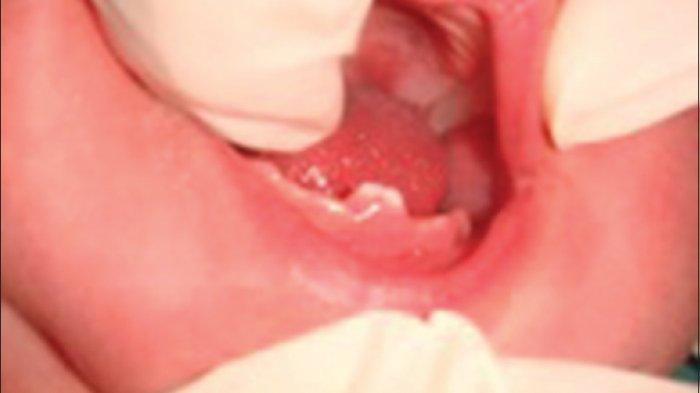

TRIBUNHEALTH.COM - Kejadian gigi yang tumbuh secara prematur pada rahang disebut dengan natal teeth apabila gigi tersebut sudah ada ketika bayi dilahirkan maupun disebut neo natal teeth apabila kemunculan gigi tersebut pada rentang kurang lebih sejak dilahirkan hingga 30 hari pasca dilahirkan.

Kondisi gigi natal teeth dan neo natal teeth lebih kecil dari gigi desidui, dan warnanya tidak seputih gigi desidui cenderung berwarna kekuningan atau kecoklatan.

Tekstur dari gigi natal teeth dan neo natal teeth tergolong sedikit kasar.